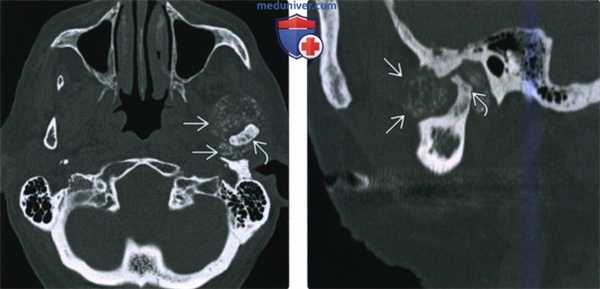

(Слева) На аксиальной КТ в костном окне визуализируется типичная хондросаркома ВНЧС с множественными кальцинатами. Мыщелок нижней челюсти слева неравномерно склерозирован, в ВНЧС и вокруг него визуализируются множественные мелкие очаговые кальцинаты.

(Справа) На сагиттальной реформатированной КТ у этого же пациента определяется деформация мыщелка. Некоторые кальцинаты, вероятно, находятся в мягкотканном компоненте за пределами сустава.

(Слева) КТ в костном окне, аксиальная проекция. Типичная хондросаркома левого височно-нижнечелюстного суаава. Мыщелок нижней челюсти склерозирован и имеет неправильную форму, внутри и вокруг сустава рассеянны множественные кальцификаты. И хотя в данном случае достаточно сложно дифференцировать заболевание от синовиального хондроматоза, в обоих случаях лечение должно быть хирургическим, а точный диагноз будет установлен после гистологического исследования.

(Справа) Реконструкция в сагиттальной плоскости, этот же пациент. Мыщелок деформирован, а часть кальцификатов находится в мягких тканях вне сустава.